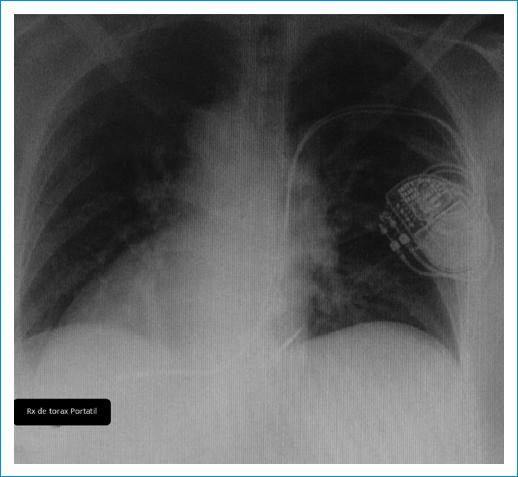

La radiografía de tórax (Fig. 2) del día siguiente no evidenció neumotórax y se identificó la posición adecuada de los electrodos. En el seguimiento clínico, la paciente refirió mejoría de la sintomatología y negó recurrencia de la alteración del estado de consciencia y eventos «convulsivos». La telemetría mostró adecuada funcionalidad del dispositivo, sin cambios significativos en los parámetros de sensado y estimulación.